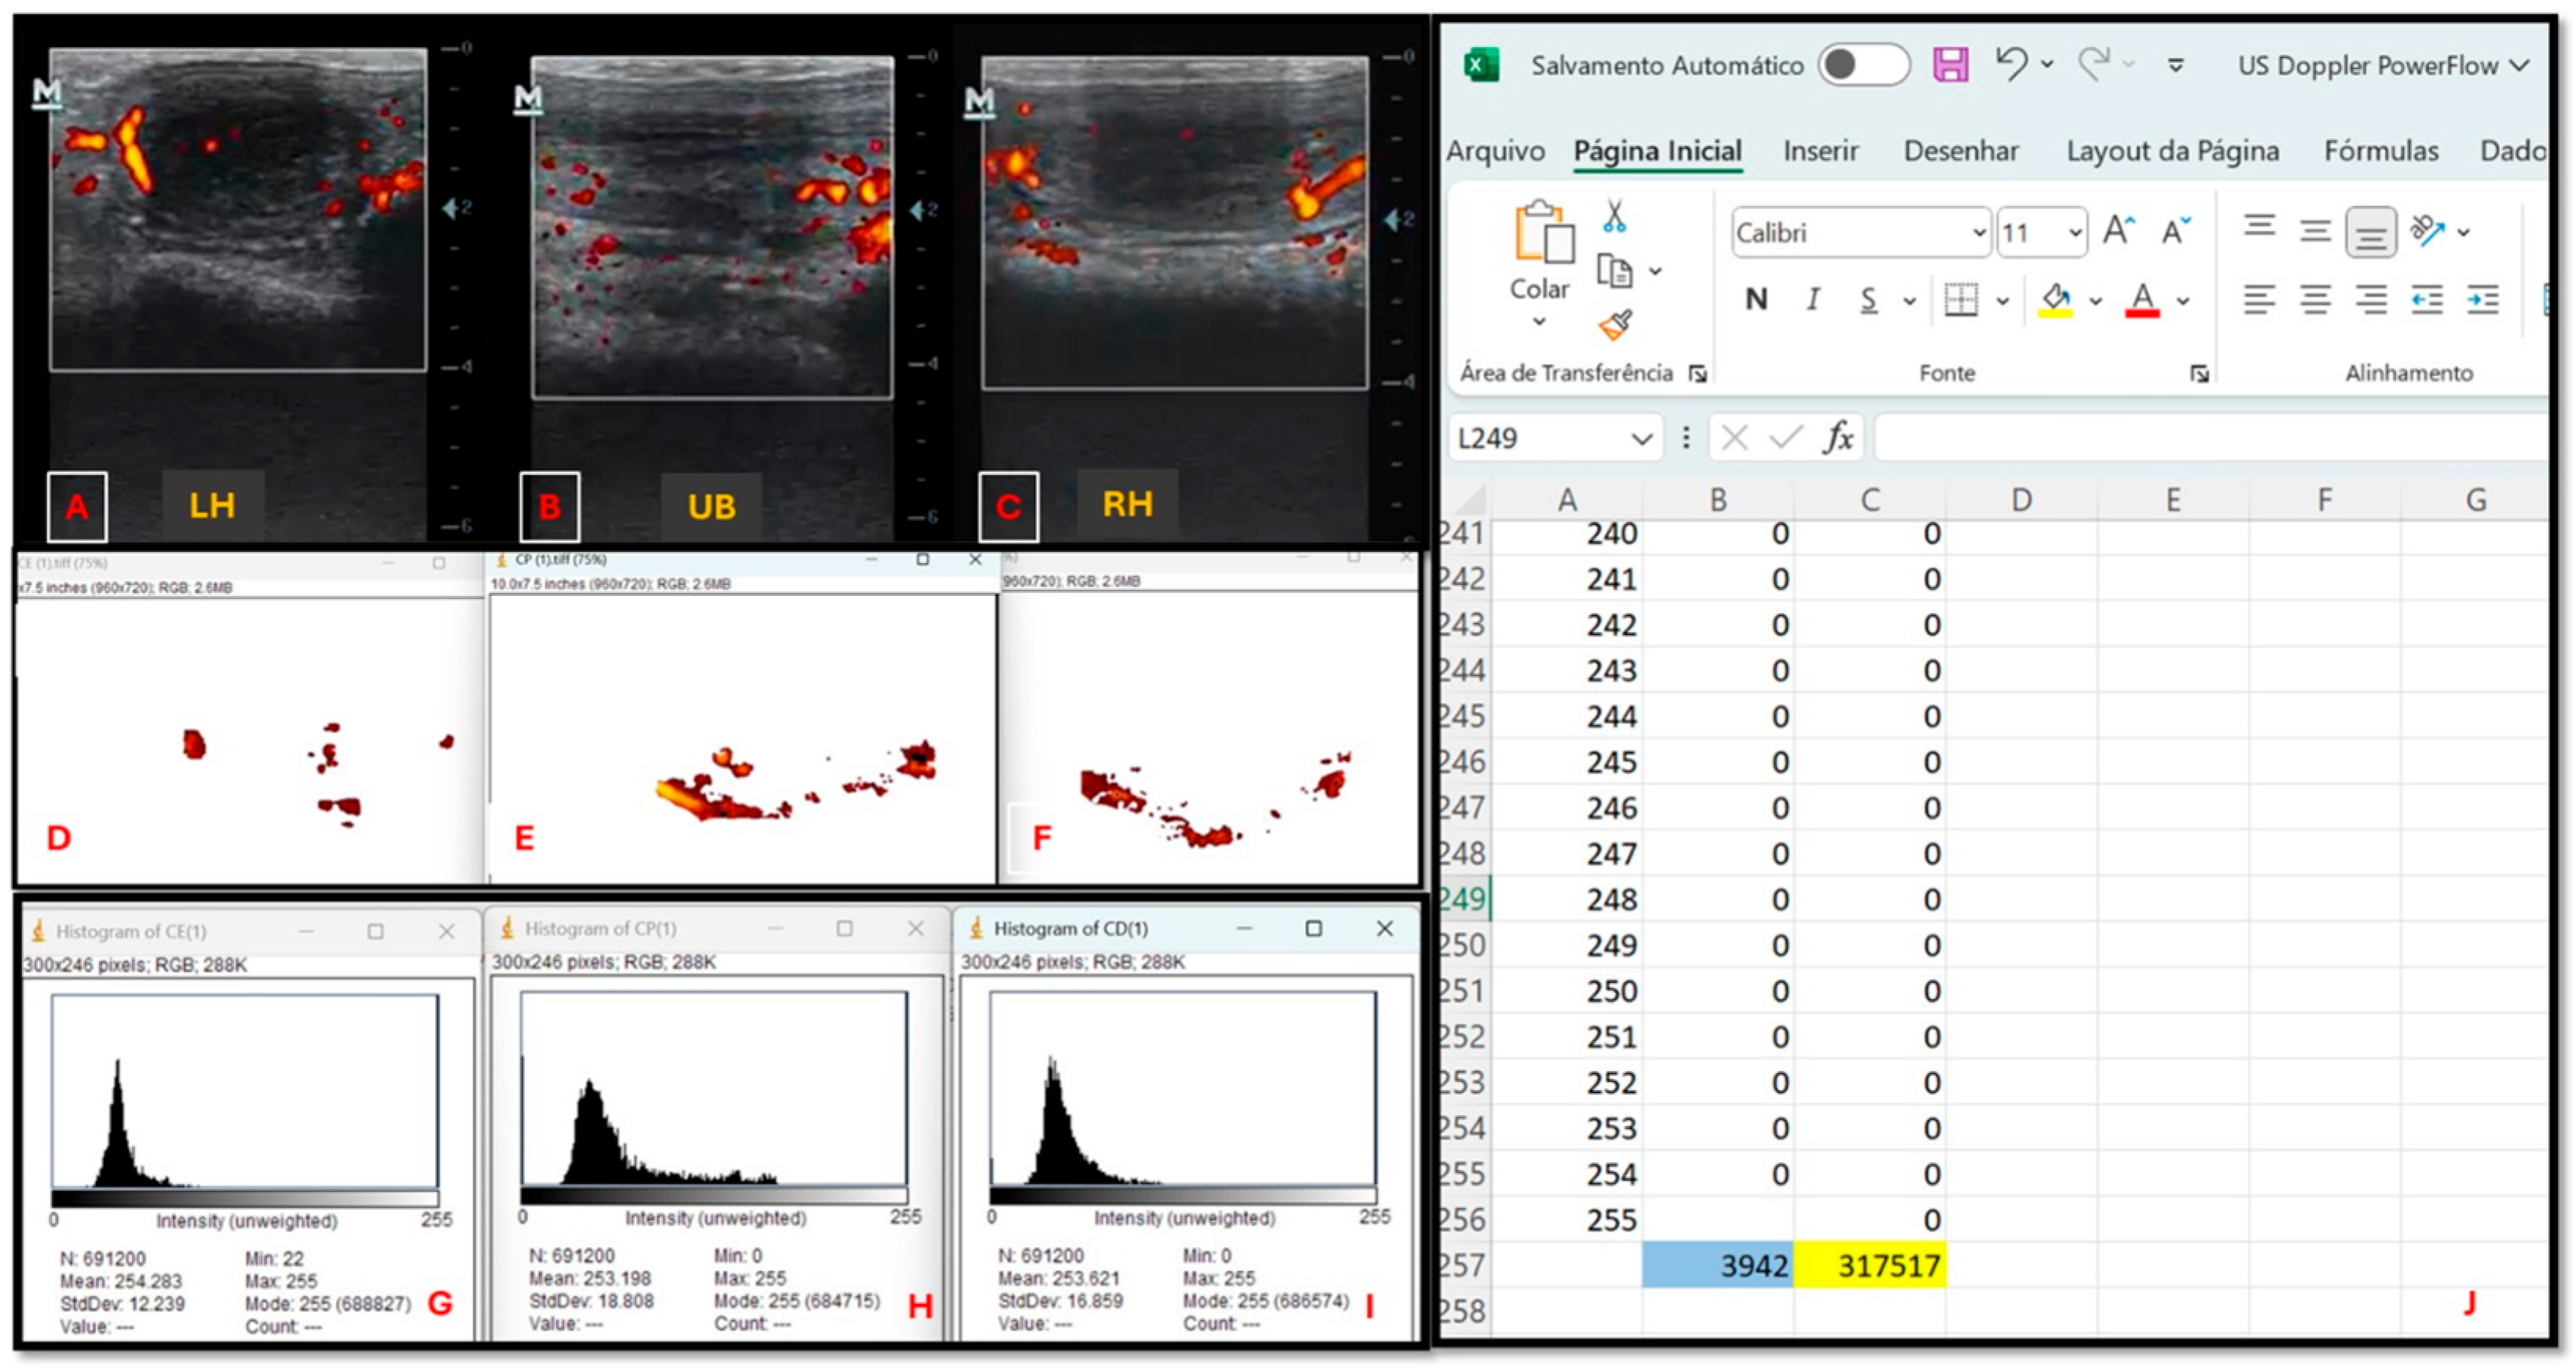

2.4.2. Ultrasound Evaluation

| n | Subjective Assessment | Number of Pixels | Intensity of Pixels | |

|---|---|---|---|---|

| Treatment Groups | ||||

| GC | 16 | Low perfusion a | 5212 ± 2452 a | 33,187 ± 170,984 a |

| GES | 15 | Low perfusion a | 5069 ± 2534 a | 436,207 ± 15,772,230 a |

| GEC | 14 | Mild perfusion b | 5475 ± 2856 a | 362,201 ± 208,170 a |